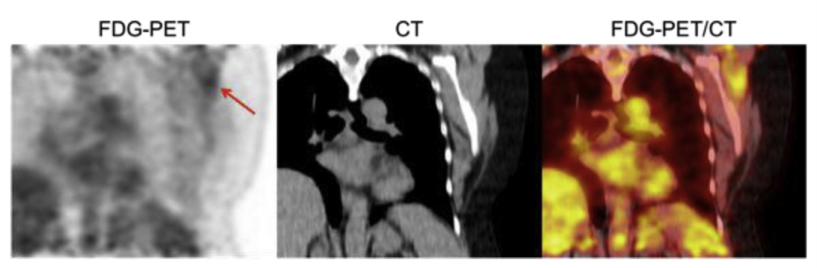

图片

由于肿瘤代谢旺盛的特点,而传统 CT 无法直接显示代谢状况,PET自身的检测特点,恰好弥补了这一缺,由PET提供病灶详尽的功能与代谢等分子信息,而CT提供病灶的精确解剖定位,两者优势互补,完美融合。一次显像就可获得全身图像,简便快捷,并兼顾了灵敏、全面、特异及定位精确。